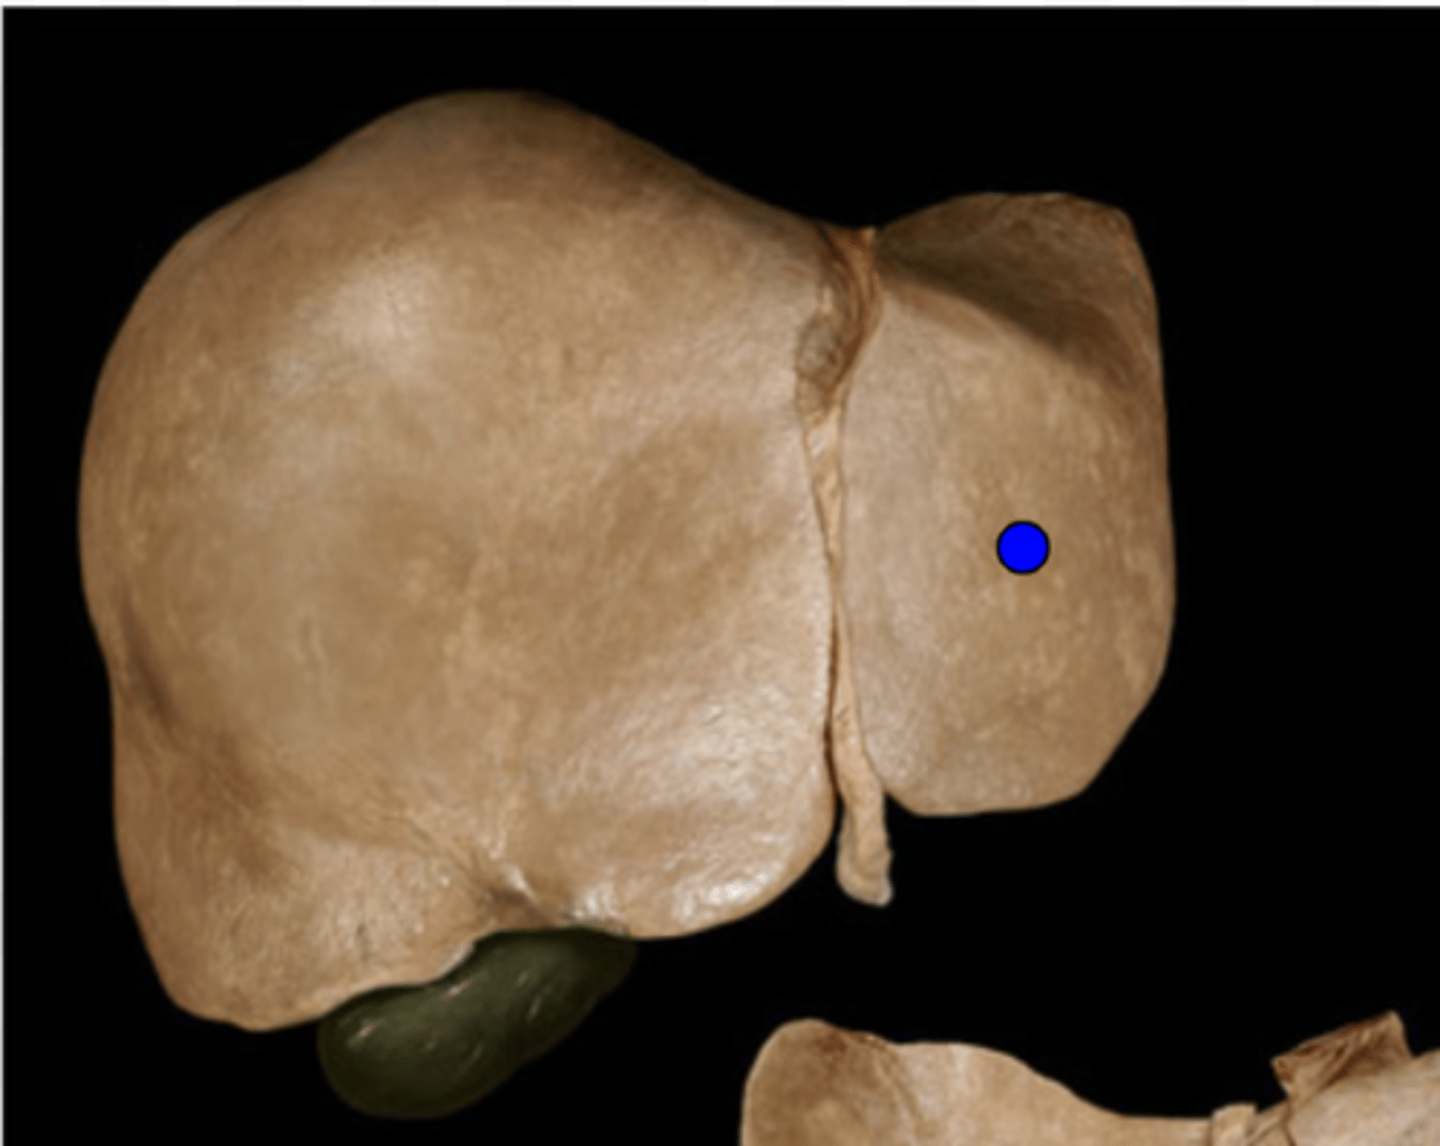

Right Lobe of Liver

Left Lobe of Liver

Caudate Lobe of Liver

Quadrate Lobe of Liver

Falciform Ligament

Ligamentum Teres

Gall Bladder